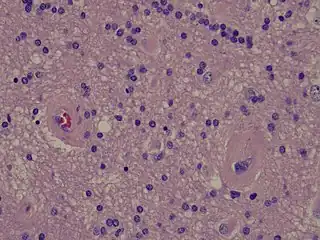

![]() Imagen histológica mostrando dos vasos ocluidos por arteriosclerosis, uno a la izquierda y el otro a la derecha de la foto. | ||